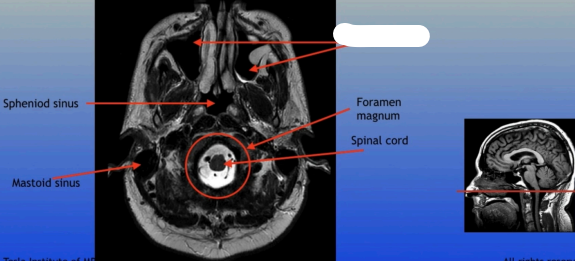

Sphenoid Sinus

Sphenoid Sinus

Mastoid Sinus

Foramen Magnum

Spinal Cord